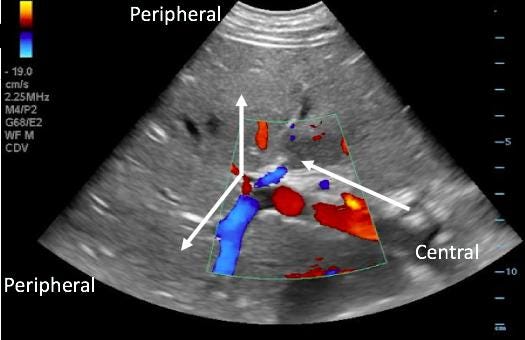

Step 4: Intrarenal Vein Doppler

How to Obtain the View

Coronal approach (xiphoid to posterior axillary line)

Visualize kidney → zoom parenchyma

Use color Doppler to identify interlobar vessels

Place Doppler gate within vein